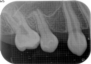

当時の歯の移植は、移植歯を抜歯したら、歯の根の表面の徹底的な清掃(掻爬)と、根管治療を口腔外で行いその歯を移植していました。しかし、それでは移植歯は移植された所の歯槽骨(もともとの歯を支える骨)とどんなに上手くいっても骨性癒着を起こします。この癒着した歯の根は時間と共に周囲の骨組織に吸収され、やがて歯の根はあとかたも無くレントゲンから消え去り、まるで乳歯が抜けるように根の無くなった歯が抜けていきます。これが5年もてば成功といわれた所以です。

現在は、ドナーとなる歯の抜歯前に移植される側の処置を終了し、ドナーの歯を抜歯するとほぼ同時に、当院では3秒以内に受容側の中にドナーの歯を入れます。これはとても速いスピードであるといえ、このスピードで確実に行う為に、いろいろな研究を行い、CTスキャンのデータを応用した現在の移植のシステムを構築致しました。

このようにして移植された歯は、歯の根の表面にある歯根膜と言う組織がほぼ完全に保存され、生着(生きた状態で移植されて機能する事)する事によって、将来矯正治療で歯を移動する事もできますし、被せもの等を行えば全く移植歯である事は気が付かれないレベルで仕上がります。